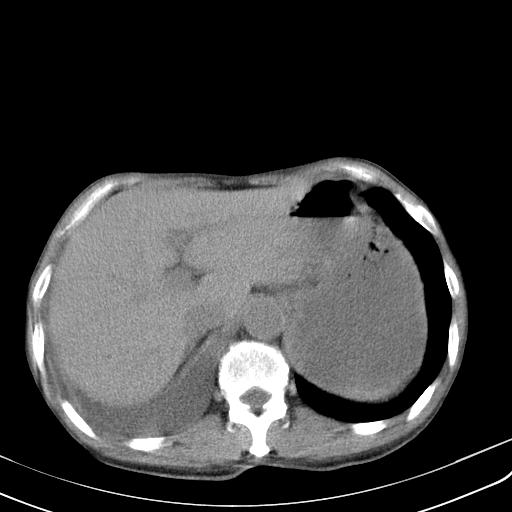

男性 75  咳嗽 一周前发热最高达39

右肺继发型tb并右侧tb性胸腔炎,右侧胸腔大量积液并右下肺膨胀不全,慢支肺气肿、多发肺大泡。建议抽胸水实验室检查并复查排除恶性在占位。

右上肺继发型肺结核,右胸腔中等量积液。

补充材料,患者2月份ct片大致正常,双侧胸腔积液,2月份抽胸水未发现ca细胞,现患者发热,痰多,各气管通畅,

1)右肺继发型肺结核。2)左肺胸膜下多发性肺大泡。3)右侧胸腔积液。